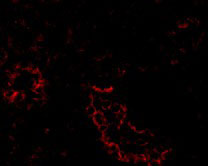

Immunofluorescence of ACE2 in Human Kidney cells with ACE2 antibody at 20 μg/mL. |